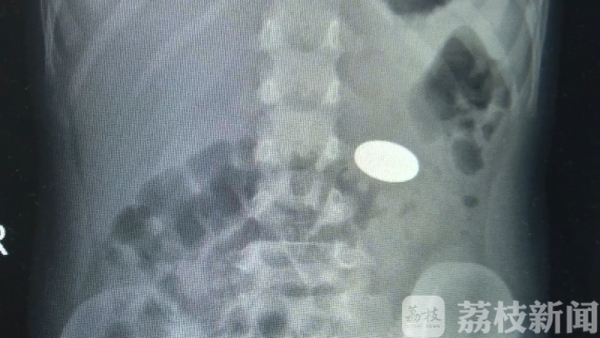

最近,扬州一名6岁男孩豆豆误把一枚一元硬币当成食物吃到肚子里去了,由于家长"马大哈",直到一个星期后,硬币才被取出,取出时硬币已经被胃液严重腐蚀。

据扬州大学附属医院儿科主治医师郁春介绍,男孩在独自玩耍的时候,不小心把硬币给吞进去了,家长发现后及时送到医院检查,做CT后发现异物在胃里面,由于硬币没有棱角,有可能自行排出,医生建议家长带孩子回去观察两天,如硬币没有排出立即来复查。然而,豆豆的家长回去之后就忘了这茬儿,直到一个星期后才想起来去医院。由于儿童幽门较窄,这时,硬币还在孩子的胃里面。